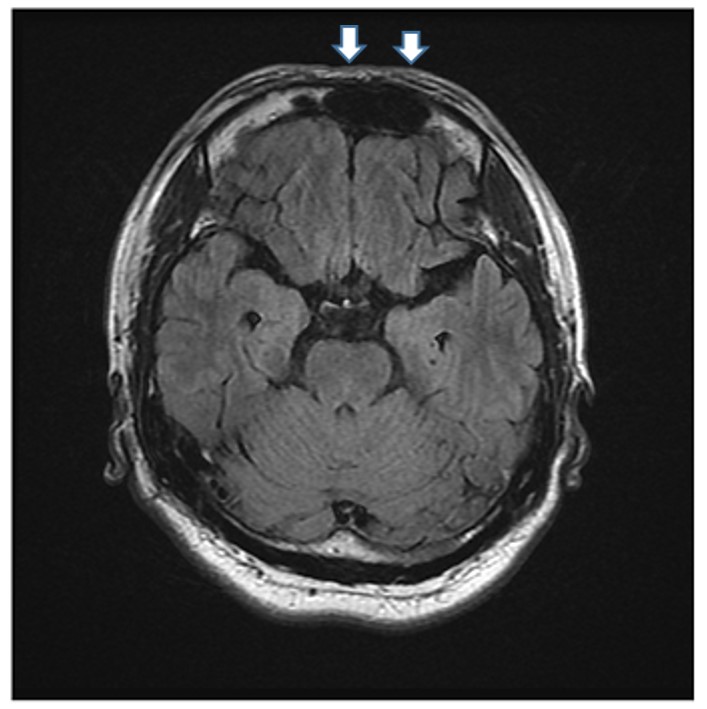

折騰一晚,隔天才接受氧氣治療,並吃了一些藥,雖症狀稍緩解,但仍是相當不舒服,一直到回到台灣,持續的頭暈頭痛才停止。但是因為仍然是間歇性頭痛,所以趕緊到永和耕莘醫院就診。想不到腦部核磁共振(MRI)檢查竟發現在顱內右前額葉有2X3公分大小的血塊(圖四、血塊如白色箭頭裡的黑色腫塊),後來繼續觀察了兩個月,在萬芳醫院追蹤的MRI檢查發現血塊終於消失了,間歇性頭痛才不再發生。

圖四:追蹤的MRI檢查發現血塊終於消失了,間歇性頭痛才不再發生。

陳先生其頭痛是因高山症所致,但因為頭痛難挨,連續撞擊頭部,再加上服用阿斯匹林過量,造成顱內局部出血導致其二度傷害。因為並非腫瘤,也非血管病變,其平常並無危險因子,例如高血壓、糖尿病、高血脂症,所以經過兩個月的追蹤,其腦部血塊完全恢復。此案例告訴我們高山症是常發生的,只要到海拔7,000-8,000英尺以上之中高海拔,就有可能發生。發生時,要盡速就醫,不能隨便過量服用止痛藥,尤其是阿斯匹林。喝酒跟過度勞累皆會促發高山症,登高山時飲食生活習慣皆須小心,豈可不慎